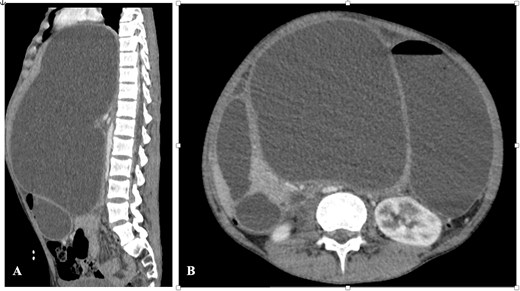

A computed tomography (CT) scan of the abdomen demonstrated a deep laceration of the body and the neck of the pancreas, with a large intrapancreatic collection displacing the liver, stomach, and inferior vena cava, with regular and well-defined contours, measuring 30 × 21.5 cm (Fig. 2).

CT abdomen—(A) sagittal section and (B) axial section showing the pseudocyst with significant organ compression.

There was no evidence of injury to any of the surrounding structures including vascular axes.